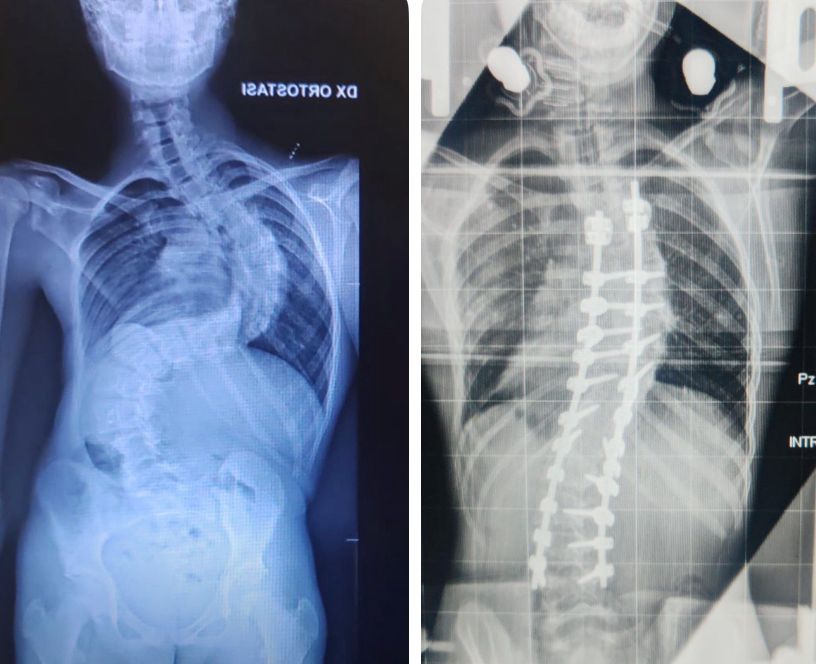

Le candeline del suo 13° compleanno le ha spente in ospedale ma il Natale potrà festeggiarlo a casa dopo oltre un mese di ricovero in ortopedia per un complesso trattamento per correggere una gravissima scoliosi di 117 gradi. L’intervento chirurgico eseguito dal dottor Andrea Piazzolla, direttore dell’unità operativa semplice a valenza dipartimentale di Chirurgia Vertebrale, gli permetterà di mettere fine a una sofferenza durata anni, con la possibilità concreta di tornare a una vita normale.

“Francesco – spiega il dottor Piazzolla – era affetto da una forma di scoliosi aggressiva, con un peggioramento impressionante: oltre 30 gradi in appena tre mesi. Una progressione rapidissima che ha imposto una preparazione preoperatoria complessa e meticolosa. Per più di un mese il ragazzo ha vissuto stabilmente in ospedale, sottoposto a trazione continua con un sistema speciale, l’halo, un dispositivo che consente di preparare progressivamente la colonna vertebrale a un intervento tanto delicato grazie al quale siamo riusciti a ridurre la scoliosi a 45 gradi”.